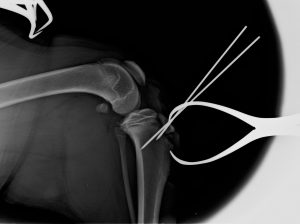

Avulsione T.T. Riduzione